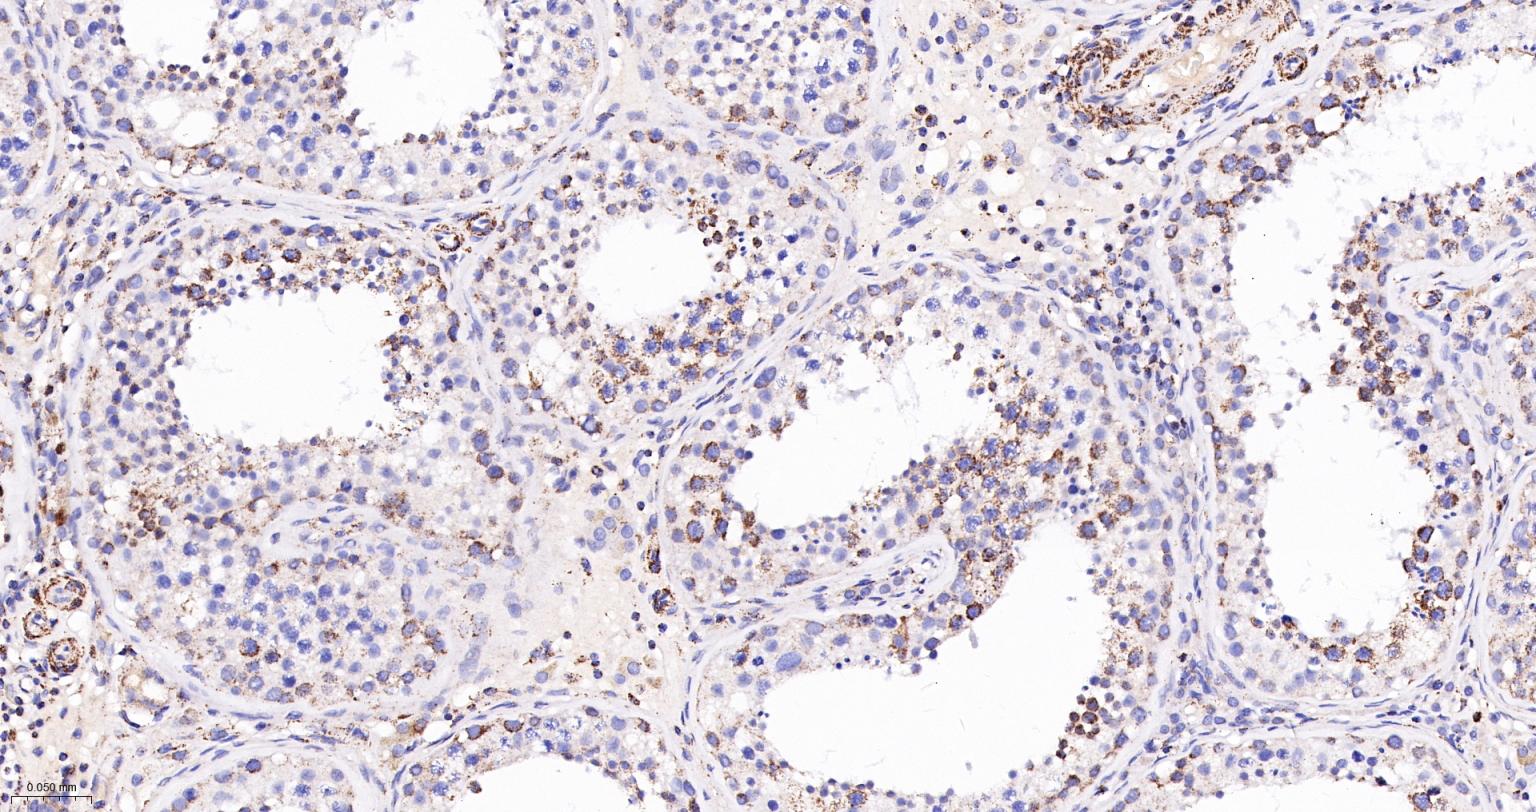

Paraformaldehyde-fixed, paraffin embedded Human Liver Cancer; Antigen retrieval by boiling in sodium citrate buffer (pH6.0) for 15 min; The section was incubated with UQCRC2 Monoclonal Antibody, Unconjugated (bsm-61649R) at 1:200 overnight at 4°C, followed by conjugation to the bs-0295G-HRP and DAB (C-0010) staining.